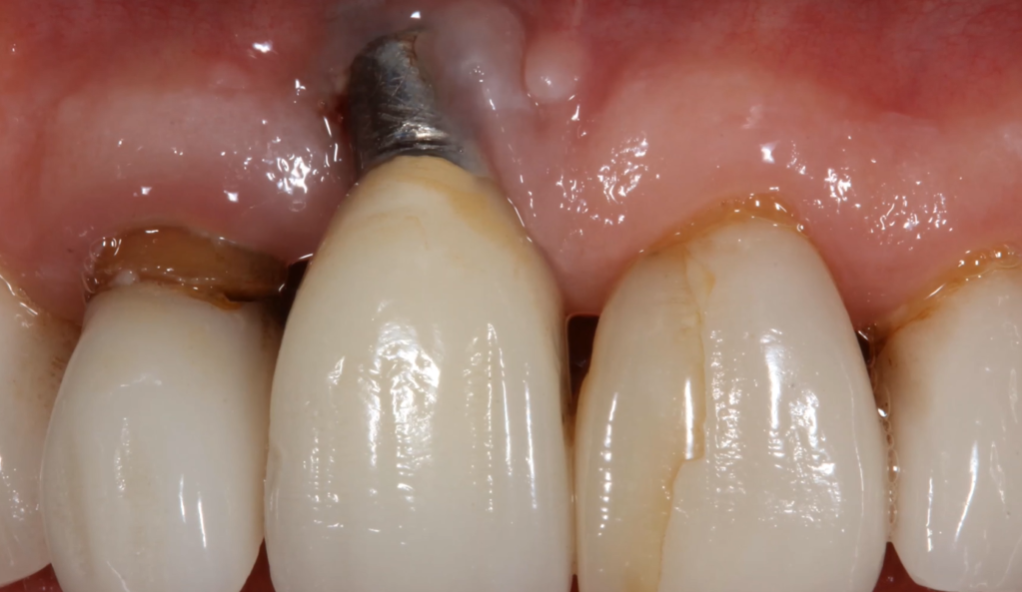

Infection (Peri-Implantitis) is one common cause. Michael, 47, experienced swelling and pain around his implant. The infection spread, making it impossible to save the implant. In such cases, removal stops the infection from damaging nearby bone and tissue. Early signs include redness, bleeding, and discomfort. Preventing this requires good oral hygiene and regular dental check-ups.

Failed Osseointegration is another reason. Sarah’s implant felt loose after three years. This failure means the implant can’t support a crown or denture properly. Without solid integration, chewing might become painful, and the implant can move. Causes include poor bone quality, smoking, or medical conditions. Removal is needed to avoid further bone loss.

Poor healing or other complications can also require removal. Some patients face issues like bone loss, implant breakage, or allergic reactions. These problems may cause pain or prevent normal function. If a complication makes the implant unstable or uncomfortable, removing it is the safest choice.